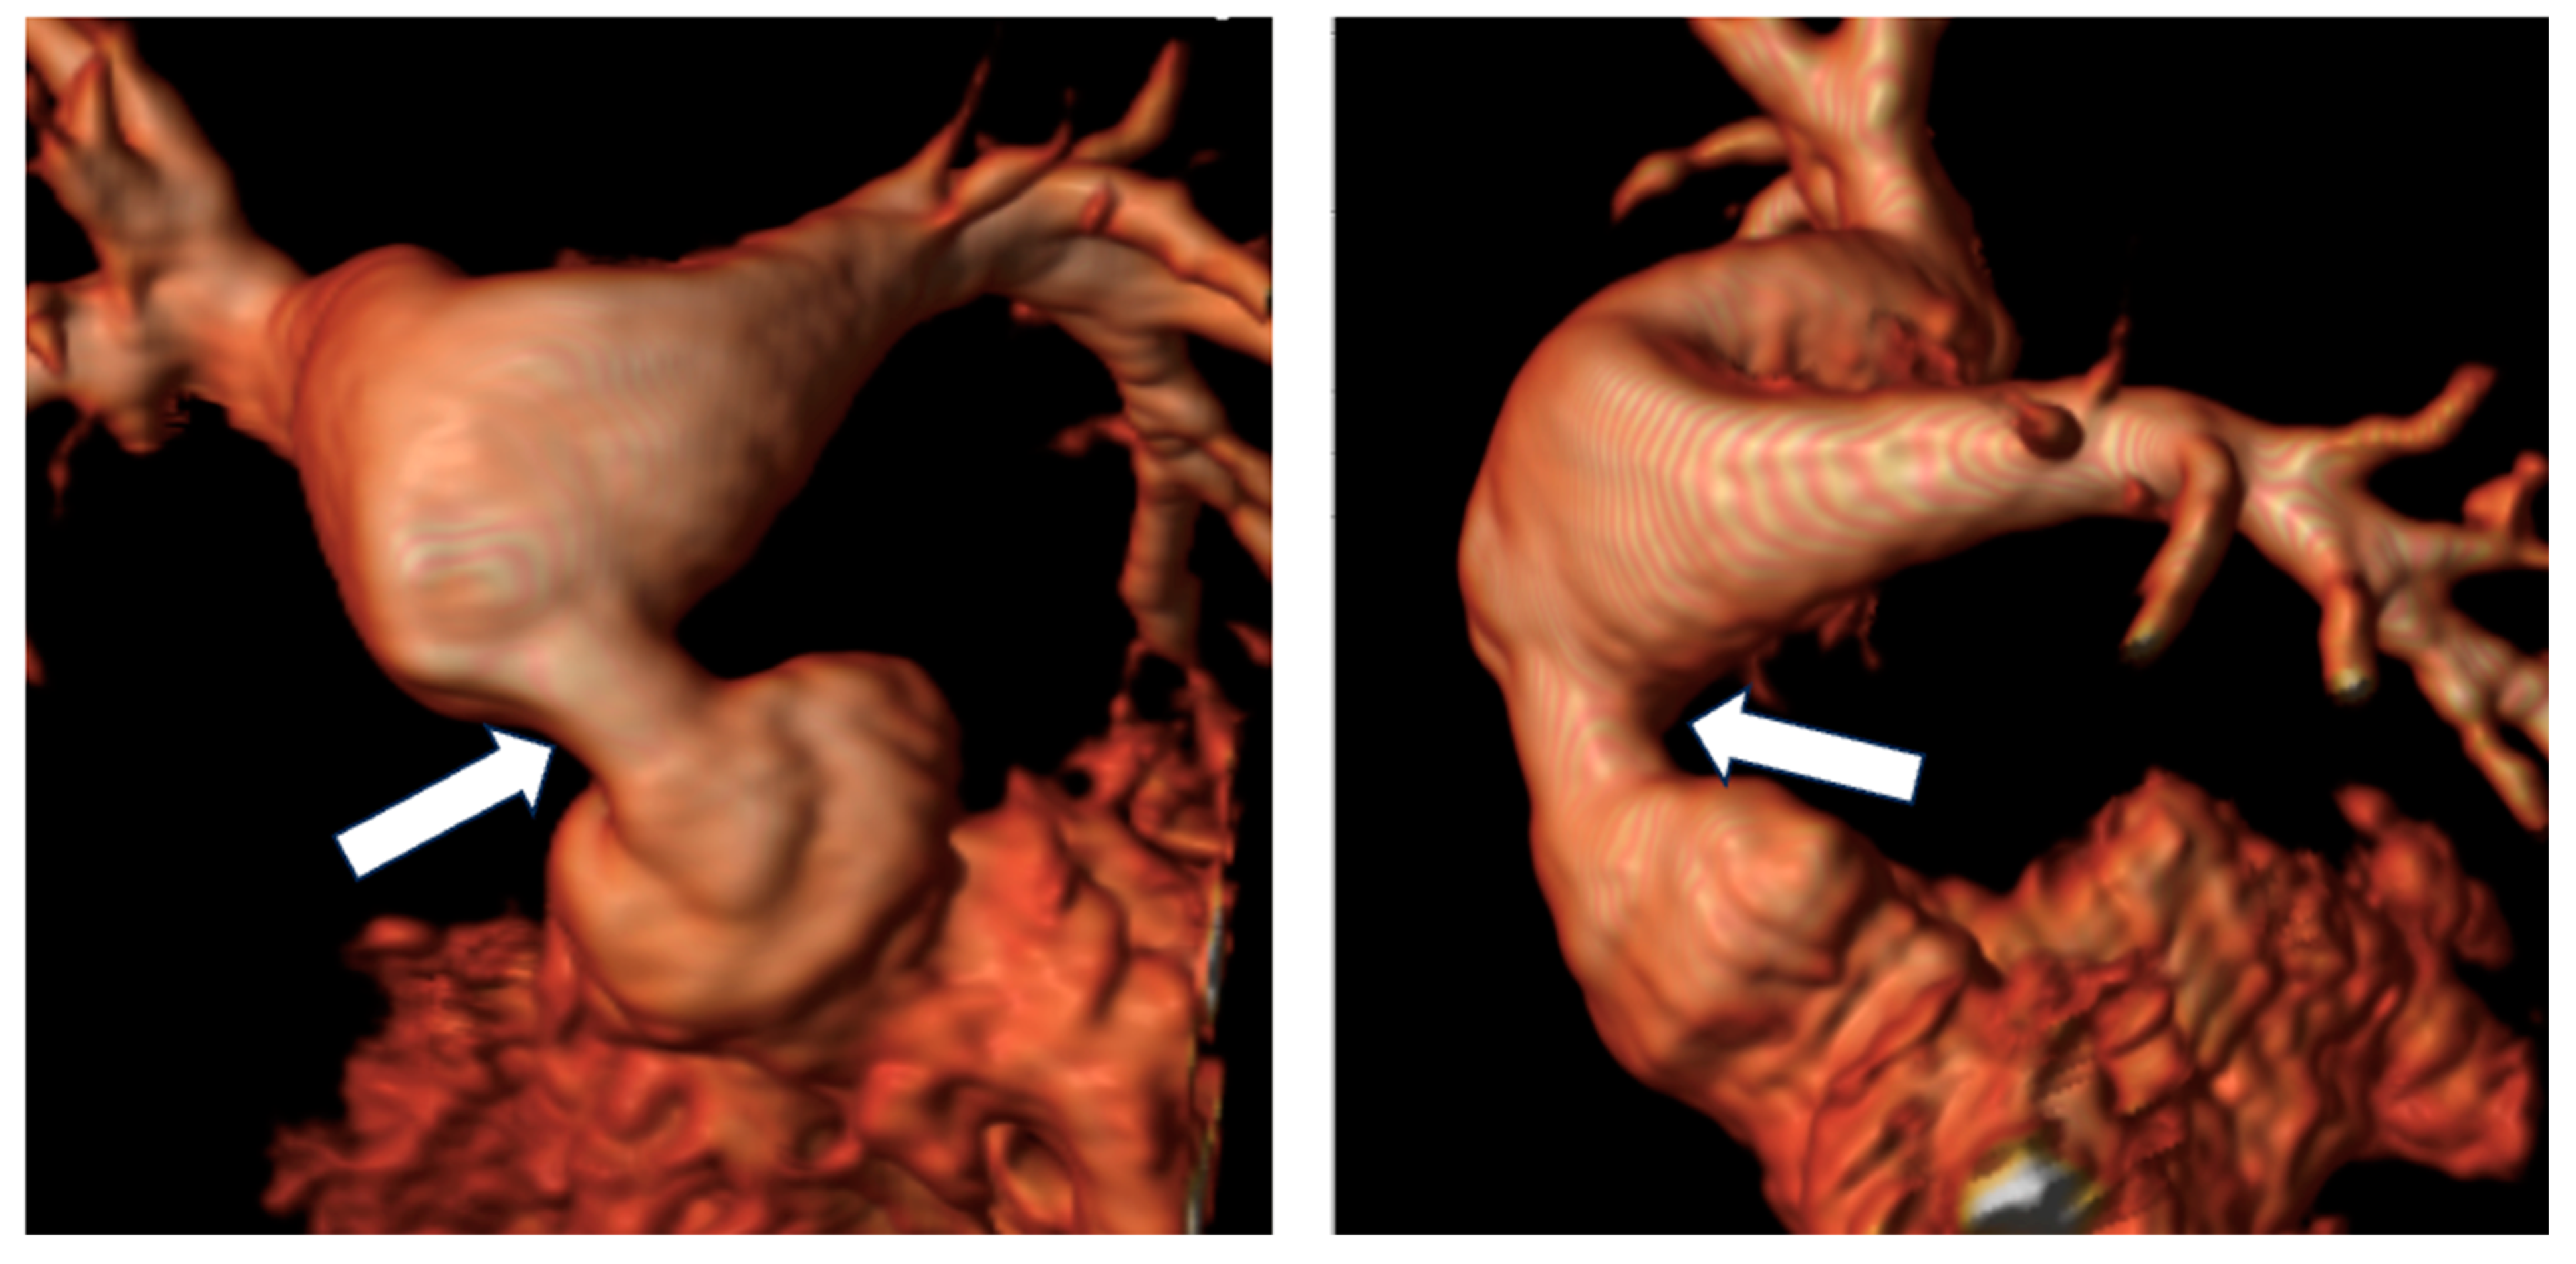

- Leo, I.; Sabatino, J.; Avesani, M.; Moscatelli, S.; Bianco, F.; Borrelli, N.; De Sarro, R.; Leonardi, B.; Calcaterra, G.; Surkova, E.; et al. Non-Invasive Imaging Assessment in Patients with Aortic Coarctation: A Contemporary Review. J. Clin. Med. 2024, 13, 28. [Google Scholar] [CrossRef]